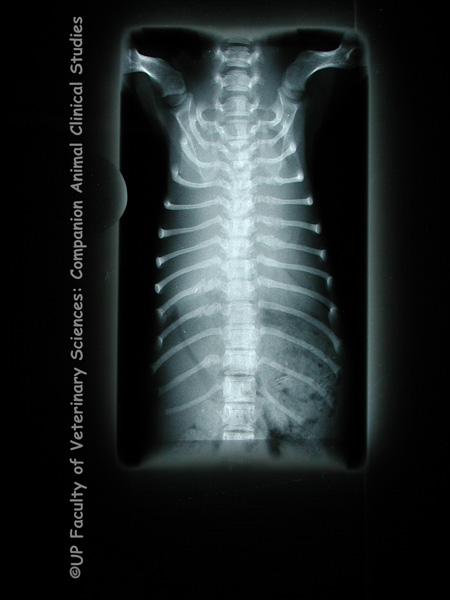

PHOTOS 1,2: Diaphragmatic hernia is the protrusion of abdominal organs into the thoracic cavity through an abnormal opening in the diaphragm. Diaphragmatic hernia may be congenital or acquired as a result of blunt trauma due to being hit by a car, high-rise syndrome, fighting, dog attacks. It may also be iatrogenic. Clinical signs include respiratory distress, borborygmus over the chest, asymmetrically quiet heart or lung sound and failure to distinguish between organs when the abdomen is palpated. Thoracocentesis and gastrocentesis may be done to relieve the dyspnoea. Immediate surgical correction is needed if the stomach has herniated, the bowel or organs are strangulated, the viscera have ruptured or if there is an inability to oxygenate after medical treatment. A traumatic diaphragmatic hernia is caused by an abrupt increase in intra abdominal pressure due to a forceful blow to the abdominal wall. The lungs then deflate rapidly resulting in a pleuroperitoneal gradient which causes the diaphragm to rupture at its weakest points. Congenital diaphragmatic hernias are due to dysfunctional development during embryogenesis. The defect causing the hernia may arise due to prenatal injury to the septum transversum or faulty development thereof. PHOTOS 3,4: Radiographic imaging may be necessary to confirm a diagnosis of a diaphragmatic hernia. In these radiographs of a Dachshund puppy, gas-filled loops of bowel can be seen crossing the diaphragm.